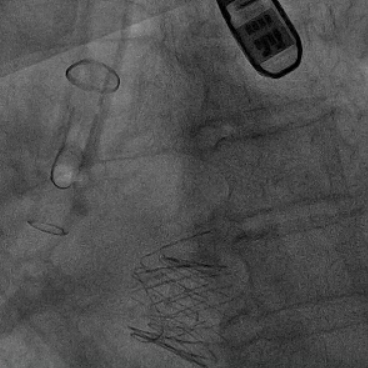

经心尖TAVR:经右侧股静脉置入临时起搏器,经右侧股动脉在患者主动脉无冠窦内放置1根6F猪尾导管进行协助定位。透视下定位后第六肋间小切口进胸,打开心包,选择心尖裸区缝制六边形荷包。心尖穿刺后将泥鳅导丝过主动脉瓣经升主动脉、主动脉弓到达降主动脉膈肌水平,通过TEE确认细导丝没有与二尖瓣腱索缠绕。单弯管交换硬导丝后,用16F扩张鞘预扩心尖穿刺处,先用24号球囊对狭窄瓣膜预扩一次(快速起搏心率:180次/分)(图3),后将 J-Valve瓣膜(25号)装入输送器,将输送器推送至主动脉根部,释放定位件,适当调整定位件角度使其进入三个主动脉窦部。通过DSA和TEE确定三个定位件准确入窦后完全释放瓣膜,撤出输送器。快速起搏心率180次/分,用24号球囊后扩一下人工瓣。通过DSA和TEE观察人工瓣膜膨胀后金属支架的形态、位置良好,无瓣周漏,前向血流速度较术前明显降低(图4-6)。撤出球囊及导丝,收紧心尖处荷包线并打结,后鱼精蛋白中和肝素,彻底止血,逐层关胸,封皮,拔出股动脉鞘并在股动脉穿刺处压迫止血。手术过程顺利,患者生命体征平稳。

图4.定位件入窦,人工瓣入座

图5.人工瓣形态位置良好,造影未见瓣周漏